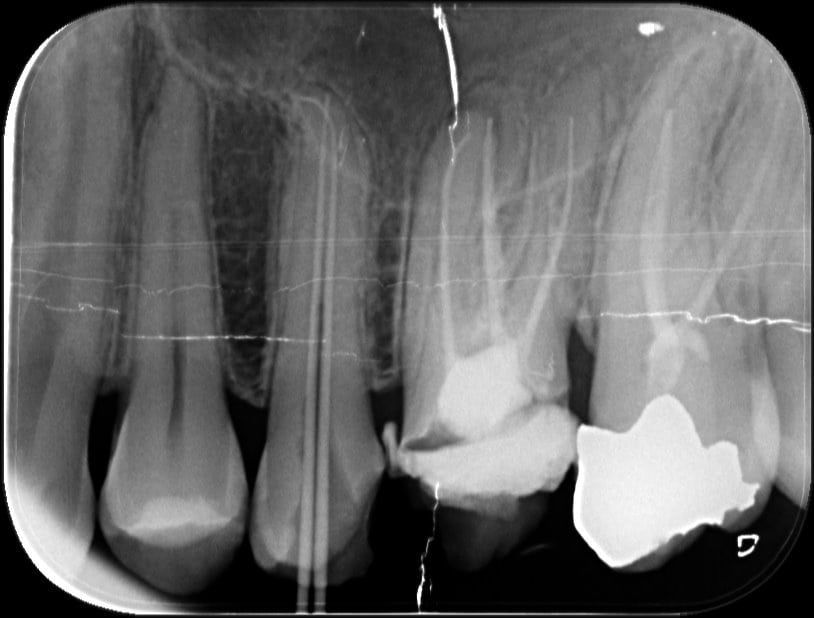

From www.researchgate.net

Master cone radiograph of 46 and 47 Fig. 6 Obturation radiograph of 46 What Is Master Cone In Rct Learn how to fill a root canal with gutta percha and root canal cement using the lateral condensation technique. Learn about the materials, techniques and principles of root canal obturation, the final step of root canal treatment. Cone fit is the first step and a good starting point for a perfect 3d obturation of the root canal system. During this. What Is Master Cone In Rct.